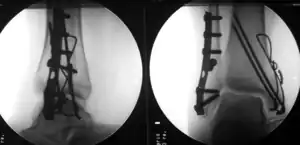

Treatment

The broad goals of treating ankle fractures are restoring the ankle joint to normal alignment, healing the fracture, and preventing arthritis.[8] The stability of the ankle joint often dictates treatment. Certain fracture patterns are stable and are thus treated without surgery similarly to ankle sprains. Unstable fractures require surgery, most often an open reduction and internal fixation (ORIF), which is usually performed with permanently implanted metal hardware that holds the bones in place while the natural healing process occurs. A cast or splint will be required to immobilize the ankle following surgery.[11] Stable ankle fractures with preserved joint alignment may be treated with non-operative measures (splinting, casting, and/or walking boot).[11]